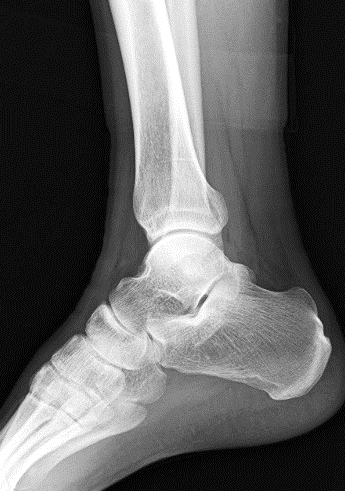

X線を体の目的部位に照射して、胸部(主に肺)や腹部、骨や関節など全身を撮影しています。

呼吸が苦しくて肺の病気を疑う、手足腰が痛くて骨折を疑う等々、まずはこちらで〝X線写真″を撮り、必要であればCTやMRIなど次の精密検査に回ることが多いです。

色々なX線画像